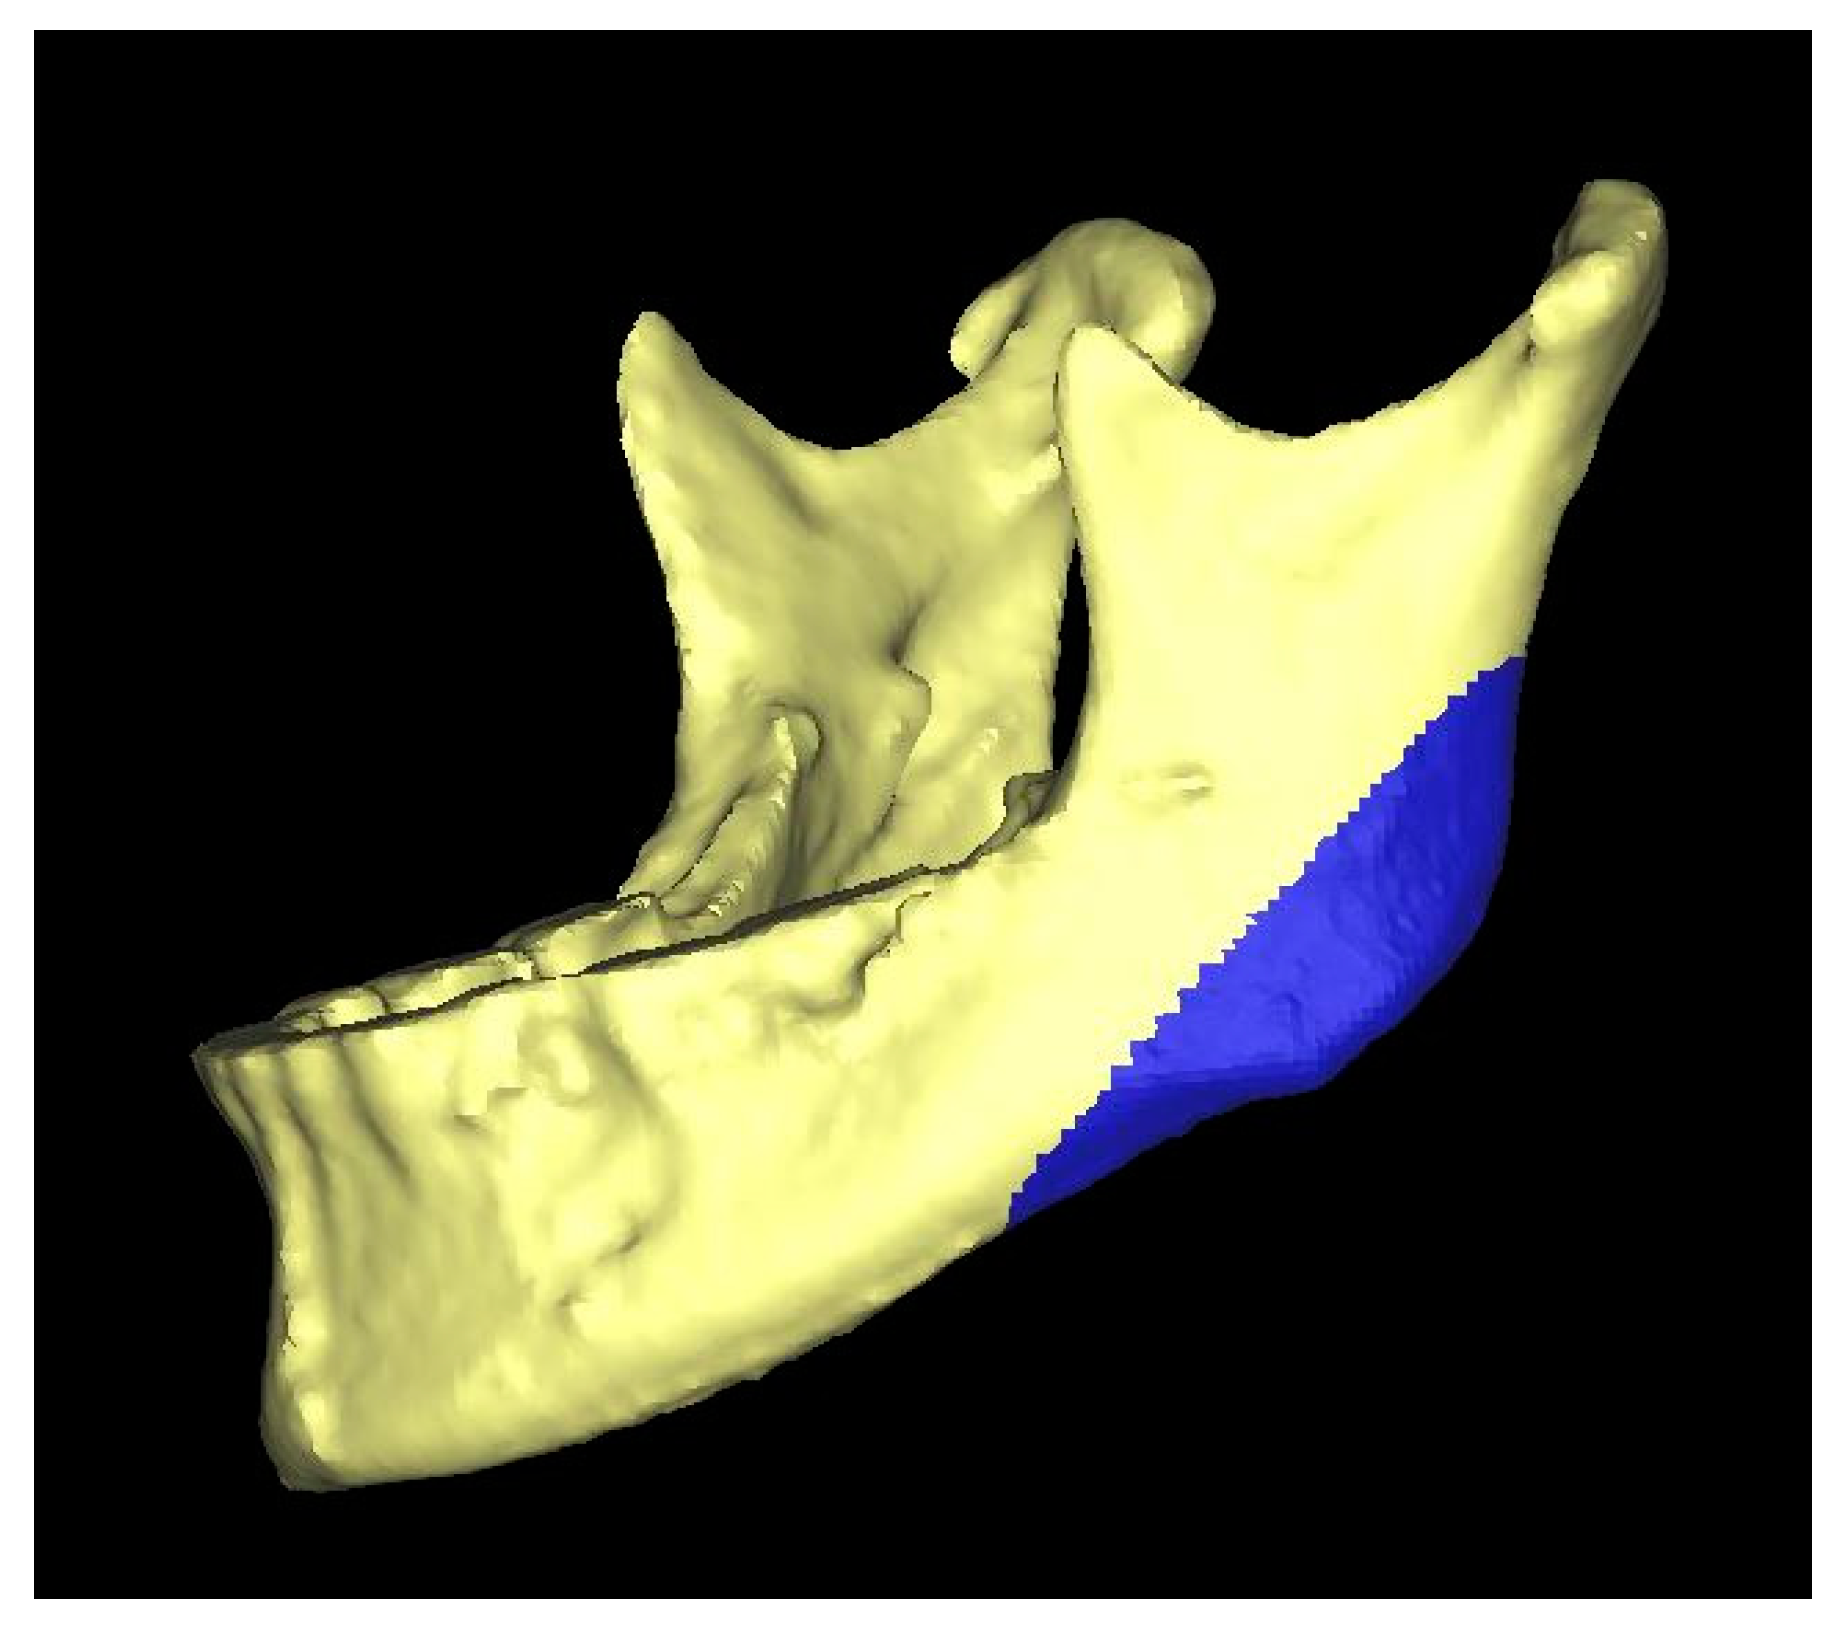

2.2. Three-Dimensional Method